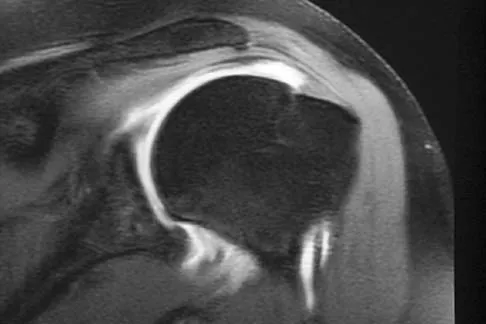

Question 28:

Correct Answer: Partial-thickness rotator cuff tear on the articular side

The MRI scan shows increased signal intensity along the deep fibers of the supraspinatus near its insertion. This is typical of tendinosis and a probable partial-thickness rotator cuff tear. Herzog RJ: Magnetic resonance imaging of the shoulder. Instr Course Lect 1998;47:3-20.